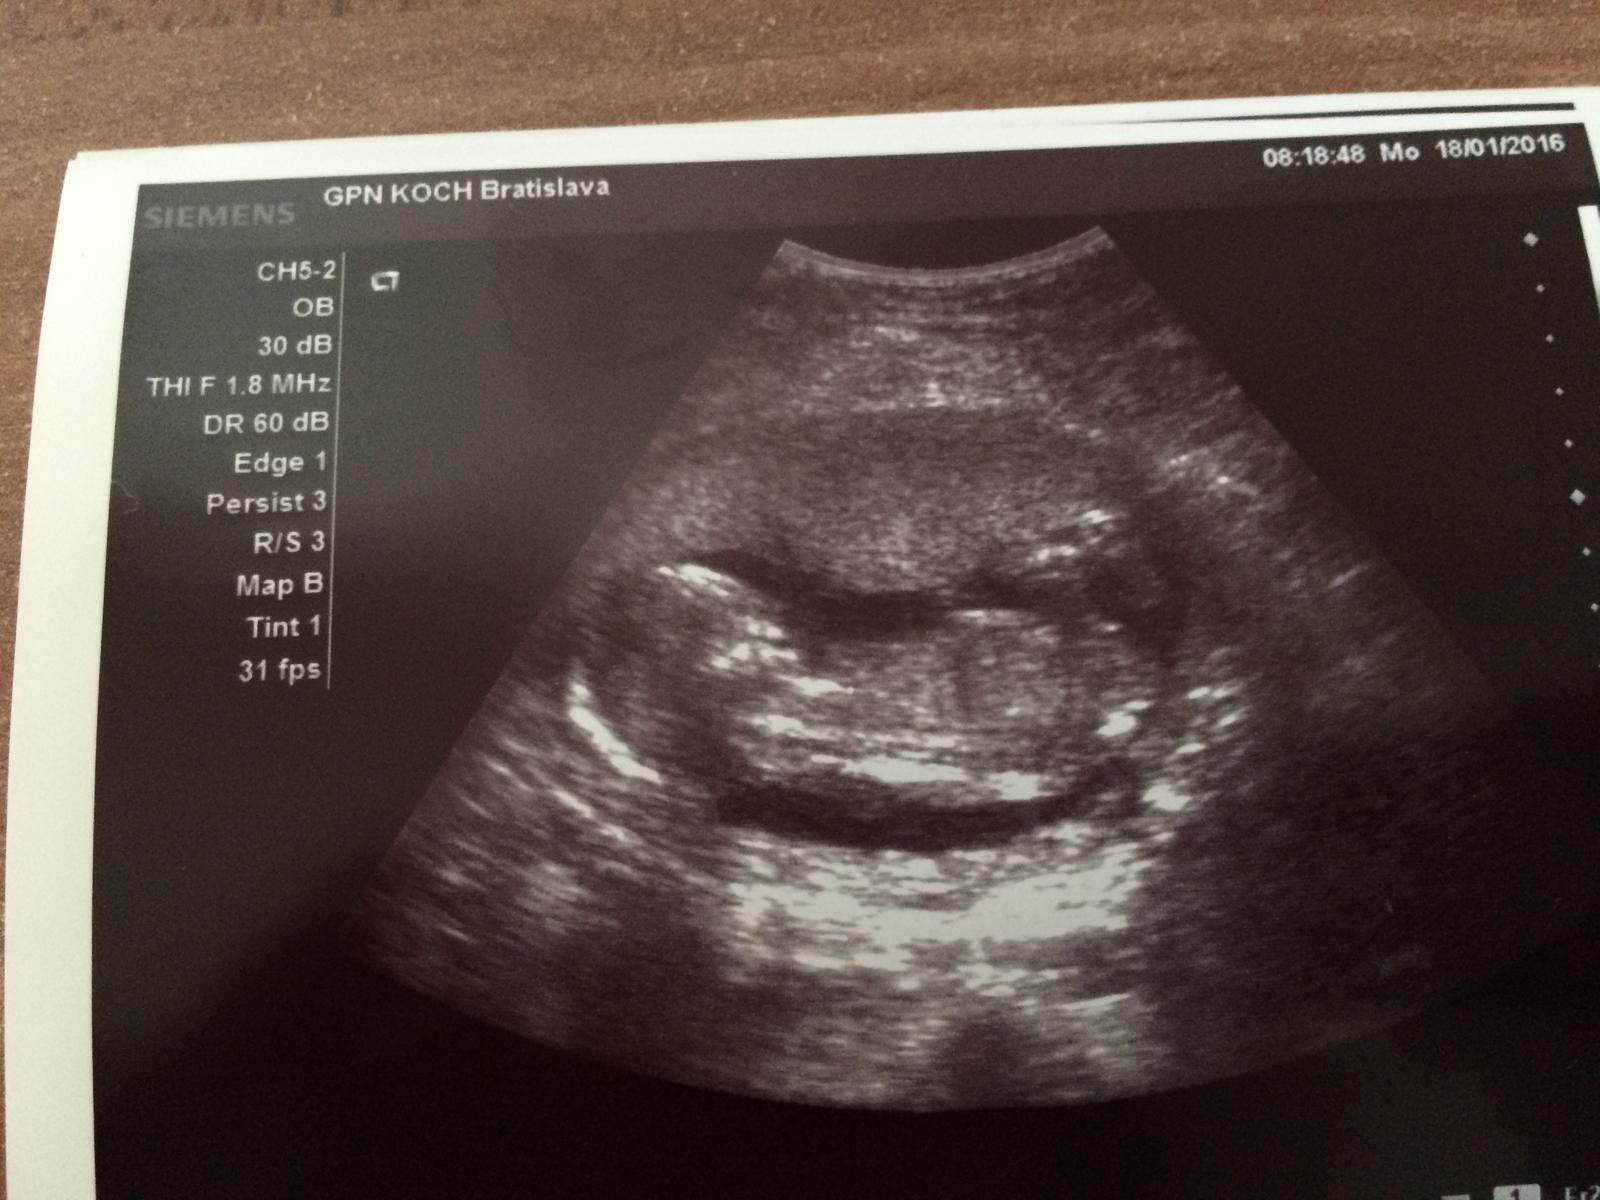

@nicolettka2126 vobec netusime ako sa bude volat 🙂, no lekar zapol sono, pomeral a hovori, kuknem este pohlavie a maly sups a nohy odseba 🙂 baby ja som spokojna, Viktorkovi hovori lekar budes mat braceka a Viktorko zacal ze Hura hura bracek. podla mna bol mimo z toho co videl 🙂 ale ja som stastna, chalana som chcela 😉

@nicolettka2126 mojko no to roztiahnutie noh, to som sa pobavila a aj ja som hned videla ze aha pipik 🙂, nakoniec nam vyslo to co sme si aj mysleli 🙂, aspon ked budeme s nimi chodit von, nebudu sa nam bit o hracky 🙂 moj sa bude hrat s autickami a tvoja s babikami 🙂

My ked sme boli na 3D tak nam dr povedala ze od hlavicky po zadocek ma mala 10,4cm a plus este nozky k tomu cize dokopy okolo 16cm 🙂